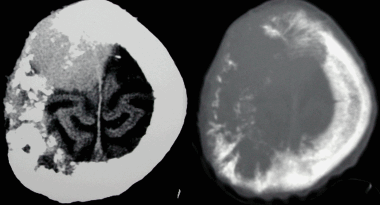

Как выглядят метастазы в головной мозг на компьютерной томографии (КТ)? Практически во всех случаях выявляется единичное (реже) либо множественные (чаще) объемные образования, которые отвечают следующим параметрам:

- Форма неправильная или сферическая

- Структура неоднородная, в центре очага может обнаруживаться область низкой плотности, обусловленная некрозом и распадом центральной части опухоли. По периферии — более плотный «ободок», который отражает активную часть опухоли, имеющую кровеносные сосуды и обладающую способностью к росту. Этот «ободок» окружен зоной низкой плотности, отражающей отек ткани мозга. Ширина данной зоны может быть различной — от нескольких мм до нескольких десятков см. Относительно однородная структура без наличия участка низкой плотности в центре и без перифокального отека. Такая структура метастаза свидетельствует о его относительной «доброкачественности»

- Отношение к прилежащим мозговым структурам. Очаги могут оказывать объемное воздействие различной степени выраженности на прилежащие отделы мозга, вызывая их смещение. Например, объемное образование в височной доле чаще всего приводит к выбуханию гиппокампа под намет мозжечка (височно-тенториальная дислокация), объемное образование мозжечка может воздействовать на мозговой ствол, приводя к его сдавлению, и т. д. Смерть при метастазах в мозг может наступить в результате сдавления мозгового ствола и нарушения дыхания и сердечной деятельности. В зависимости от локализации, вторичные очаги могут приводить к сдавлению церебральной ликворной системы, приводя к развитию окклюзионной гидроцефалии (резкому расширению центральных ликворных пространств на фоне повышения внутримозгового давления при окклюзии путей оттока ликвора из полости черепа)

- Тип роста. Метастазы могут обладать инфильтративным типом роста (расти, разрушая окружающие ткани) и экспансивным типом (расти, раздвигая окружающие ткани). В первом случае они чаще всего дают осложнения в виде кровоизлияния, то во втором обычно обуславливают возникновение дислокаций.

- Параметры контрастного усиления. Типичные вторичные опухоли в головном мозге увеличивают свою плотность в периферических отделах при внутривенном введении контраста, принимая вид «кольца», «полукольца», «спирали». Гораздо реже наблюдается равномерное контрастное усиление очага. Обычно центральная зона опухоли не усиливается, как и область перифокального отека.

Метастазы головного мозга, фото. На КТ с контрастным усилением у пожилой пациентки (в верхнем ряду слева) с жалобами на головные боли выявлены множественные объемные образования в левом полушарии мозга, интенсивно накапливающие контрастное вещество. Образования имеют характерную форму в виде «кольца». На изображениях в нижнем ряду и вверху справа определяются множественные очаги в головном мозге: отчетливо видны округлые образования с более плотным «ободком» по периферии, располагающиеся в левой теменной доле.